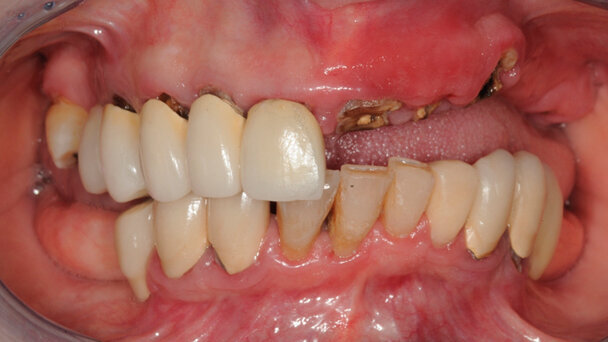

Il paziente presenta una malocclusione scheletrica di II classe biretrusa ipodivergente. In questa tipologia di soggetti il mascellare superiore è spesso piccolo e arretrato. In condizione di edentulia il processo di atrofia centripeta riduce ulteriormente il perimetro di arcata. È importante verificare sul piano verticale sagittale e trasversale se i rapporti scheletrici tra una forma di arcata superiore inferiori sono congrui. In caso negativo si rischia di dover compensare protesicamente la riduzione scheletrica. Dal punto di vista protesico questa situazione può creare ingombro eccessivo dell’area neutra, difficoltà alla fonazione, ridotta capacità di esegiure le procedure di igiene orale.

Esempio 2

Paziente con mascellare corretto sagittalmente ed eccesso verticale e sagittale della mandibola, III classe scheletrica iperdivergente. In questo caso lo studio delle dimensioni verticali intermascellari consente la valutazione di dove va inserita la linea del sorriso, in funzione dell’esposizione labiale e del piano osseo corticale. La valutazione di questi parametri riduce il rischio di creare una linea del sorriso non evidente o di compensare con elementi dentari protesici troppo lunghi.